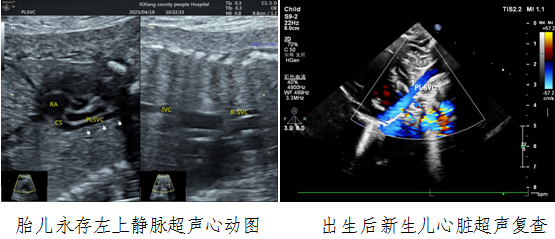

病例一,30岁,孕22w+,G2P1,既往产检未见胎儿心脏结构异常。2023年4月到西乡县黑料网

例行常规产前超声检查,黑料网对口帮扶贾玄慧医生,超声发现胎儿存在先天大血管发育异常——永存左上腔静脉,指导孕妇进行产前咨询及产后随访。胎儿出生后1天,贾玄慧医生立即对该新生儿进行了心脏复查,结果确诊永存左上腔静脉诊断明确。